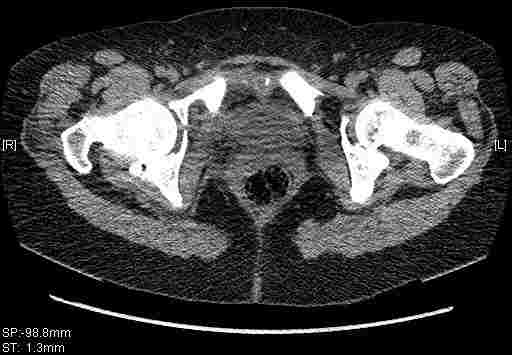

Удалось сегодня вывести пациентку в соседнюю больницу, где есть кт. Срезы сделаны только горизонтальные.

|